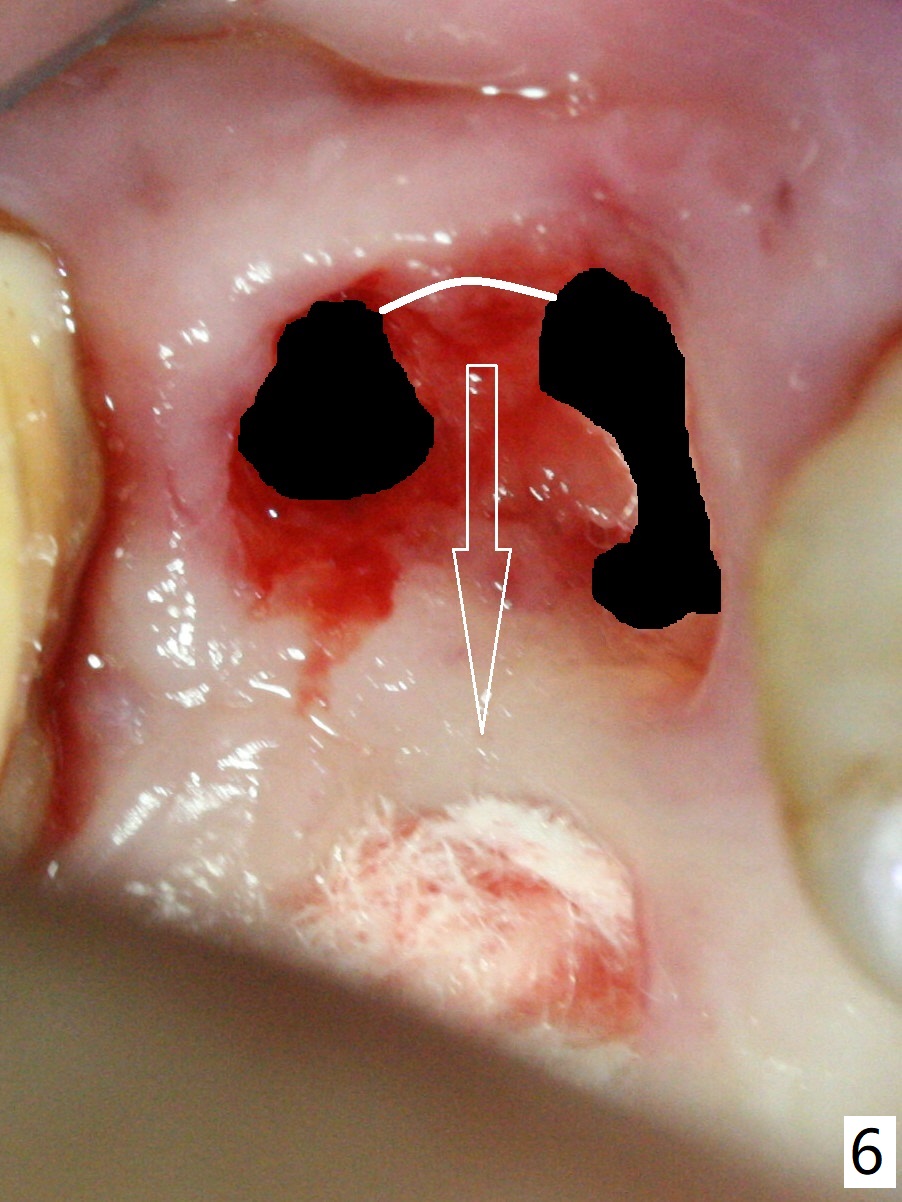

Push Septal Gingiva Palatal

The tooth #3 has gingival recession moderate buccally (Fig.1) and severe palatally (Fig.2 P). The remaining bone height is estimated 4 mm (Fig.3). After extraction and debridement, the 3 sockets are packed with 2% Lidocaine 1:50,000 Epinephrine saturated gauze (Fig.4). When the gauze is removed from the buccal sockets (Fig.5 black area), the buccal portion (B) of the septal gingiva (*) is sectioned from the buccal gingiva (Fig.6 curved white line) and elevated from the underlying septal bone and pushed palatally (arrow). The septal gingiva (including the buccal portion) will be the palatal soft tissue wall of the subsequent osteotomy, providing blood supply to allograft to be placed. In short, the septum (through the buccal socket) will be the osteotomy site.